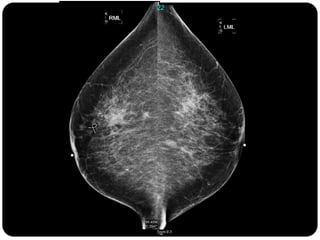

Paciente femenina de 66 años con historia clínica de 1er gesta antes de los 30 años y antecedentes de lactancia positiva, presenta una lesión palpable en la mama derecha. Los estudios radiológicos indican un diagnóstico de bi-rads 5, con biopsias revelando adenocarcinoma lobulillar infiltrante en la glándula mamaria derecha y adenocarcinoma ductal in situ en la izquierda. El caso fue evaluado por las doctoras Jacqueline Preciado Vargas y Beatriz E. González Ulloa.